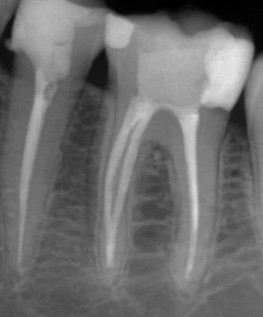

Кхалил Абаноуб Адли Абдуллах: портфолио (4)